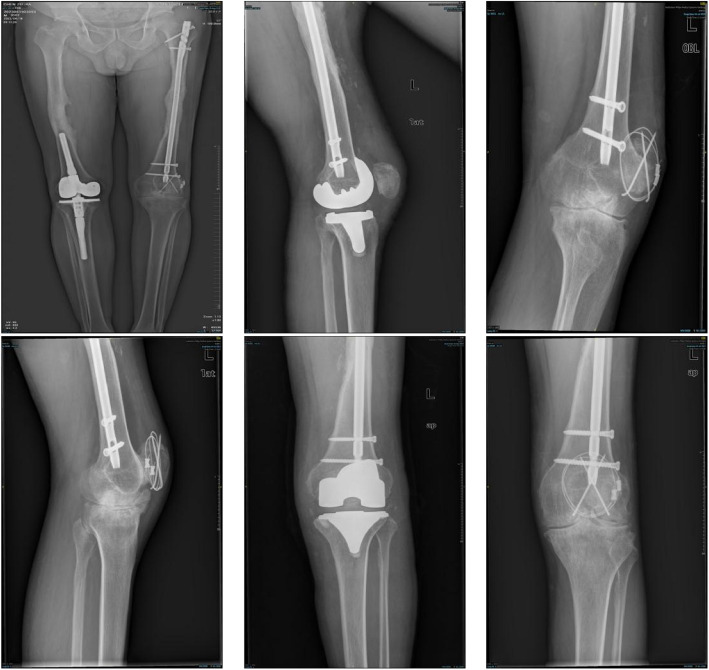

Methods: Between January 2008 and December 2021, 22 male patients with ankylosed knees in the extended position due to hemophilia underwent TKA. The average age of the patients was 41.3 years (range, 19 to 52 years), and the average hospital stay was 33.4 days (range, 14 to 50 days). TKA was performed using quadriceps tendon Z-lengthening plasty, staged osteotomy, and comprehensive soft-tissue release. A variety of methods were used to evaluate the postoperative clinical outcomes and complications, including range of motion (ROM) assessment, Visual Analogue Scale (VAS), Knee Society Score (KSS), and the Western Ontario and McMaster Universities Osteoarthritis Index (WOMAC).

Results: At the last follow-up, the average KSS increased from 75.14 ± 34.63 before surgery to 148.41 ± 27.74 (P < 0.001), the ROM increased from 0 to 86.14 ± 24.69 (P < 0.001), the WOMAC score changed from 28.05 ± 11.20 before surgery to 10.82 ± 11.00 (P < 0.001), and the average VAS score decreased from 2.86 ± 1.86 to 0.73 ± 1.20 (P < 0.001).

Conclusion: Although the recovery of range of motion is lower than normal and there is a relatively high incidence of complications, TKA can still significantly improve the flexion and extension functions, mobility, and quality of life of patients with ankylosed knees.